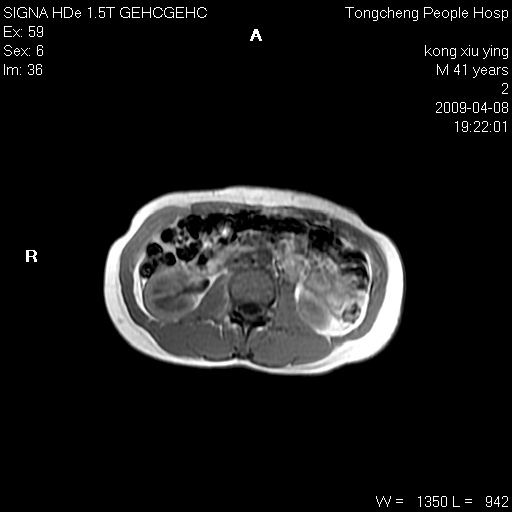

标题: CL1008:【经典】胆囊石榴籽样结石。 [打印本页]

标题: CL1008:【经典】胆囊石榴籽样结石。

女,41岁。健康体检——彩超提示:胆囊显示不清。平素健康,无不适感。

腹部mr扫描及mrcp,图像如下: